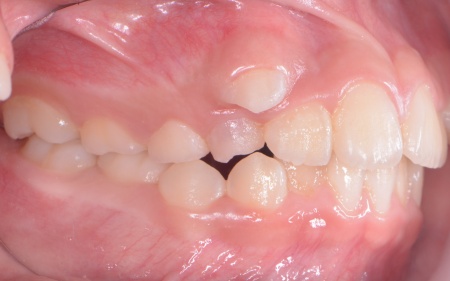

拝見したところ、上の犬歯が歯列の外側に飛び出すように生えている、いわゆる八重歯でした。

さらに、上下の歯全体がデコボコに生えている「叢生(そうせい)」と呼ばれる状態で、これは歯が正しい位置に並ぶためのスペースが不足していることが原因だと考えられます。

このまま放置して顎の成長が完了してから矯正治療を行う場合、歯を並べるスペースを確保することが難しく、永久歯を抜く処置が必要になるケースがあります。

患者様のご家族は「将来的な抜歯はできるだけ避けたいので、今のうちに治療をしたい」と希望されたため、成長期の段階で歯列を広げ、歯が並ぶスペースを確保する小児期の矯正治療「1期矯正」を提案しました。